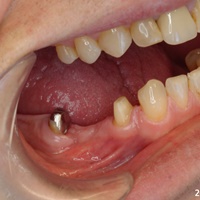

Dziesieć lat po wykonaniu mostu pacjent zgłosił się z recesją dziąsła i próchnicą korzenia. Zamiast ekstrakcji wykonano hemisekcję i nowy most.